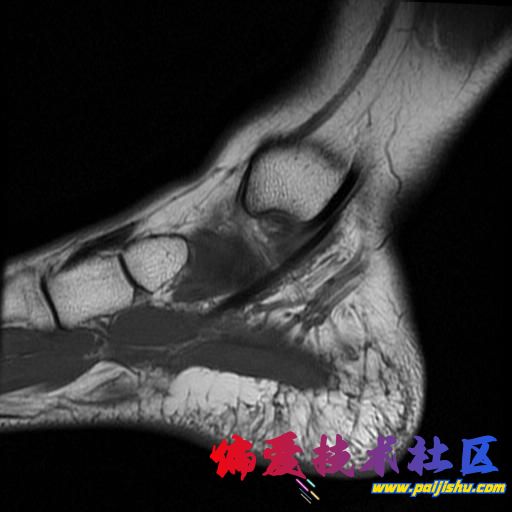

庆幸骨头没事,单肌腱拉伤,静养中